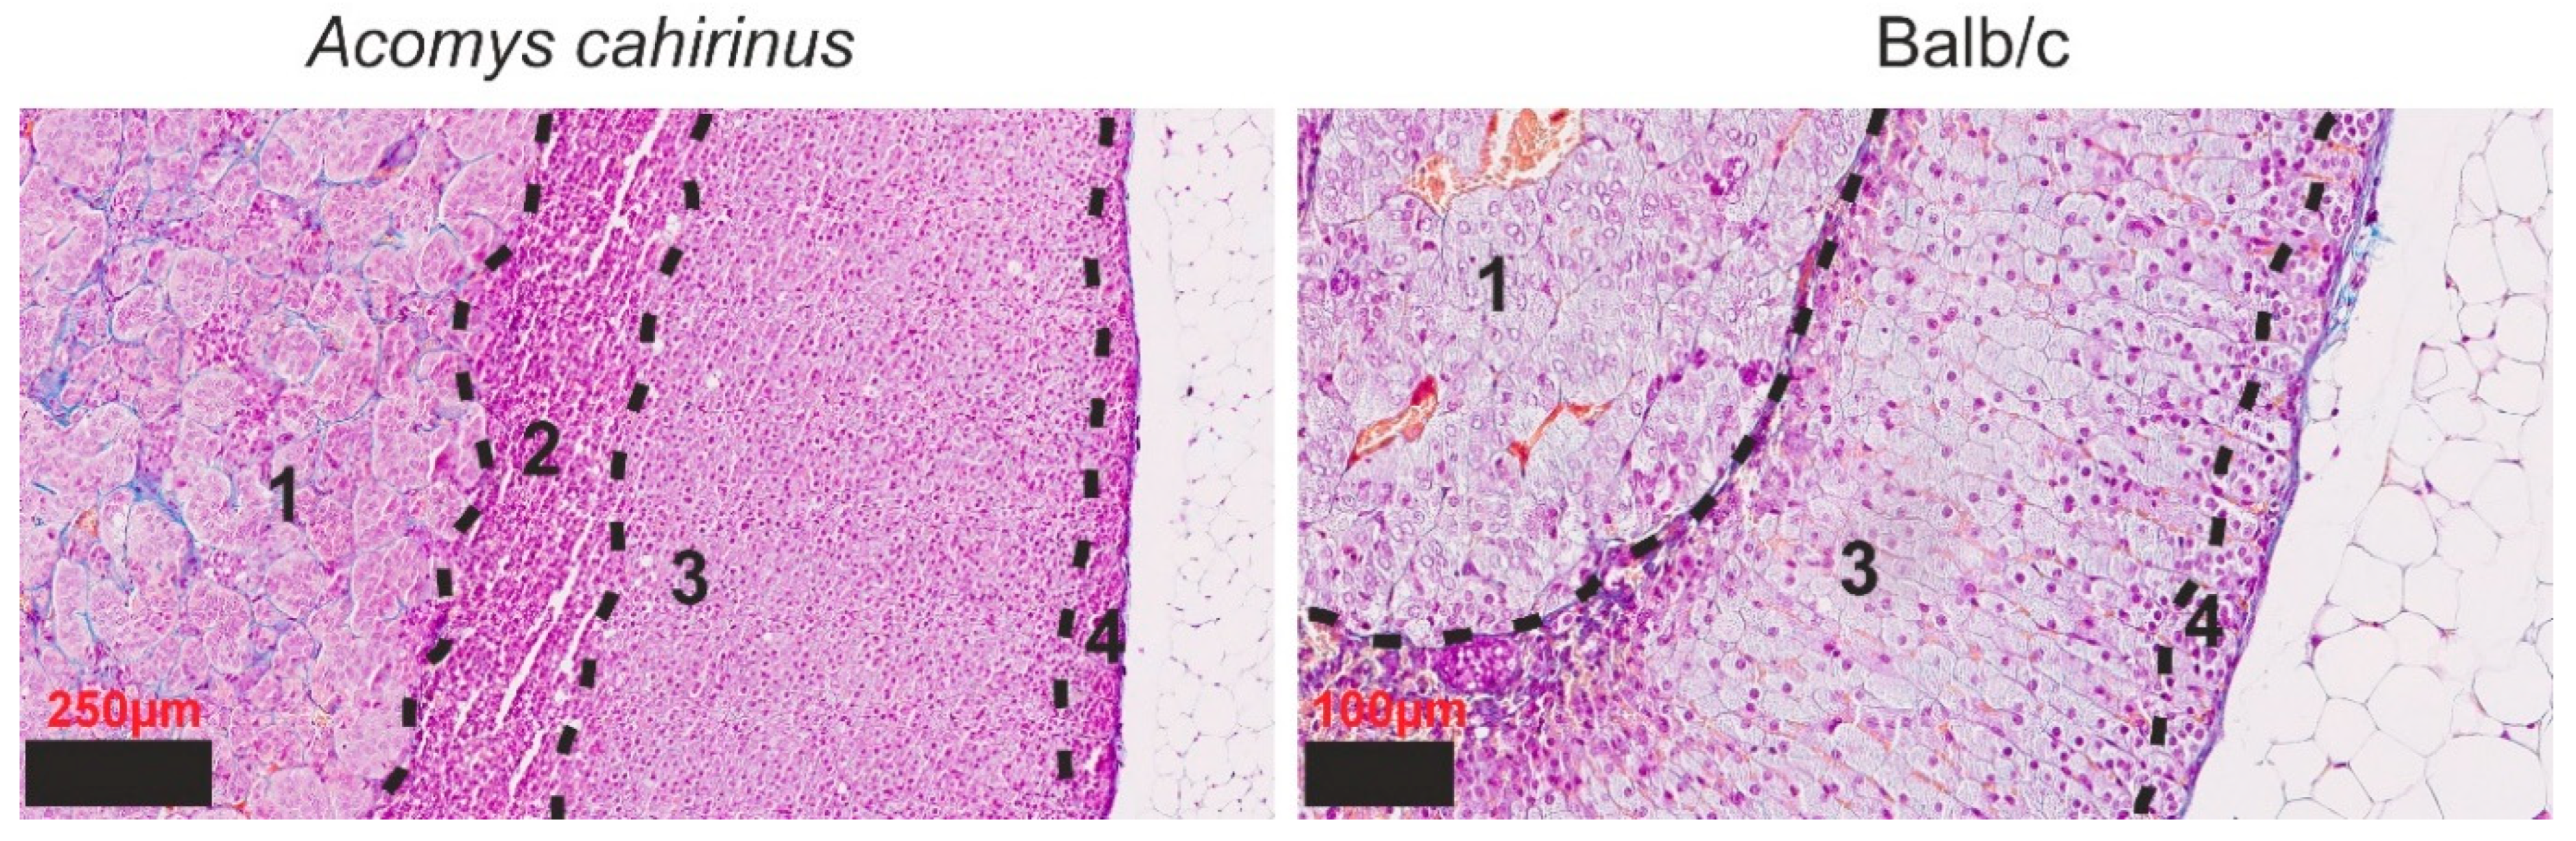

3.1. Histological Examination